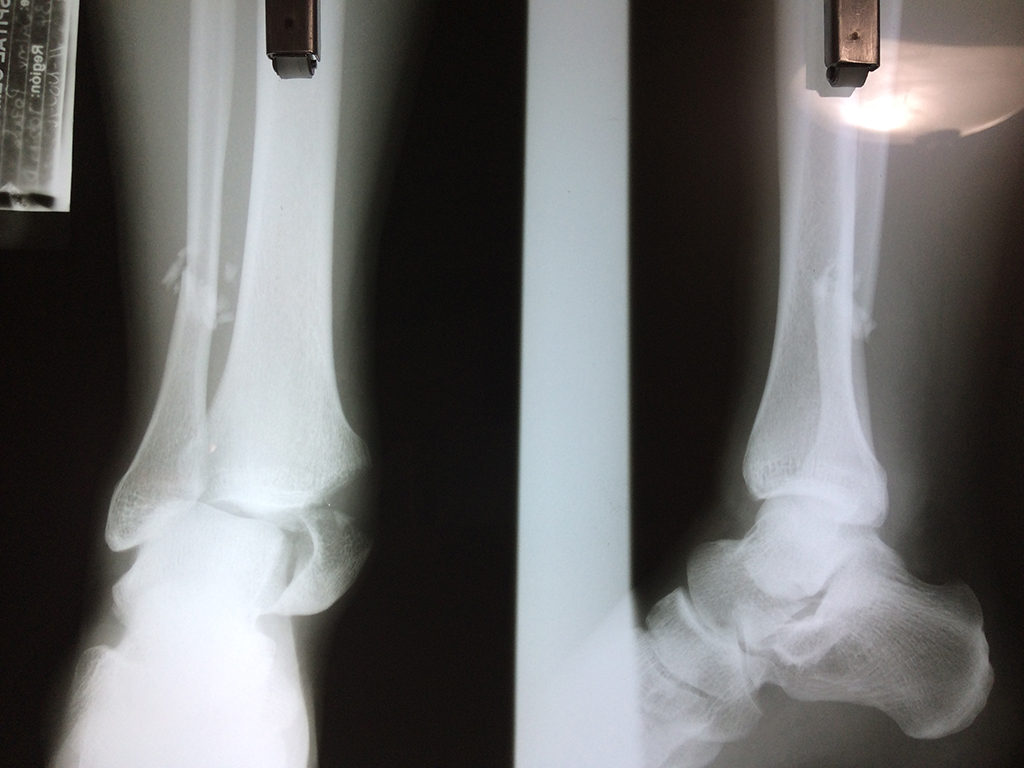

Cirugías de Tobillos

Una fractura de tobillo es la rotura de uno o más de los huesos del tobillo. Estas fracturas pueden ser:

Algunas fracturas de tobillo pueden requerir cirugía si:

- Los extremos de los huesos están desalineados entre sí (desplazados).

- La fractura se extiende hasta la articulación del tobillo (fractura intra-articular).

Cuando se necesita cirugía, es probable que esta implique el uso de clavijas de metal, tornillos o placas para sostener los huesos en su lugar mientras la fractura se consolida. Los elementos de soporte pueden ser temporales o permanentes.